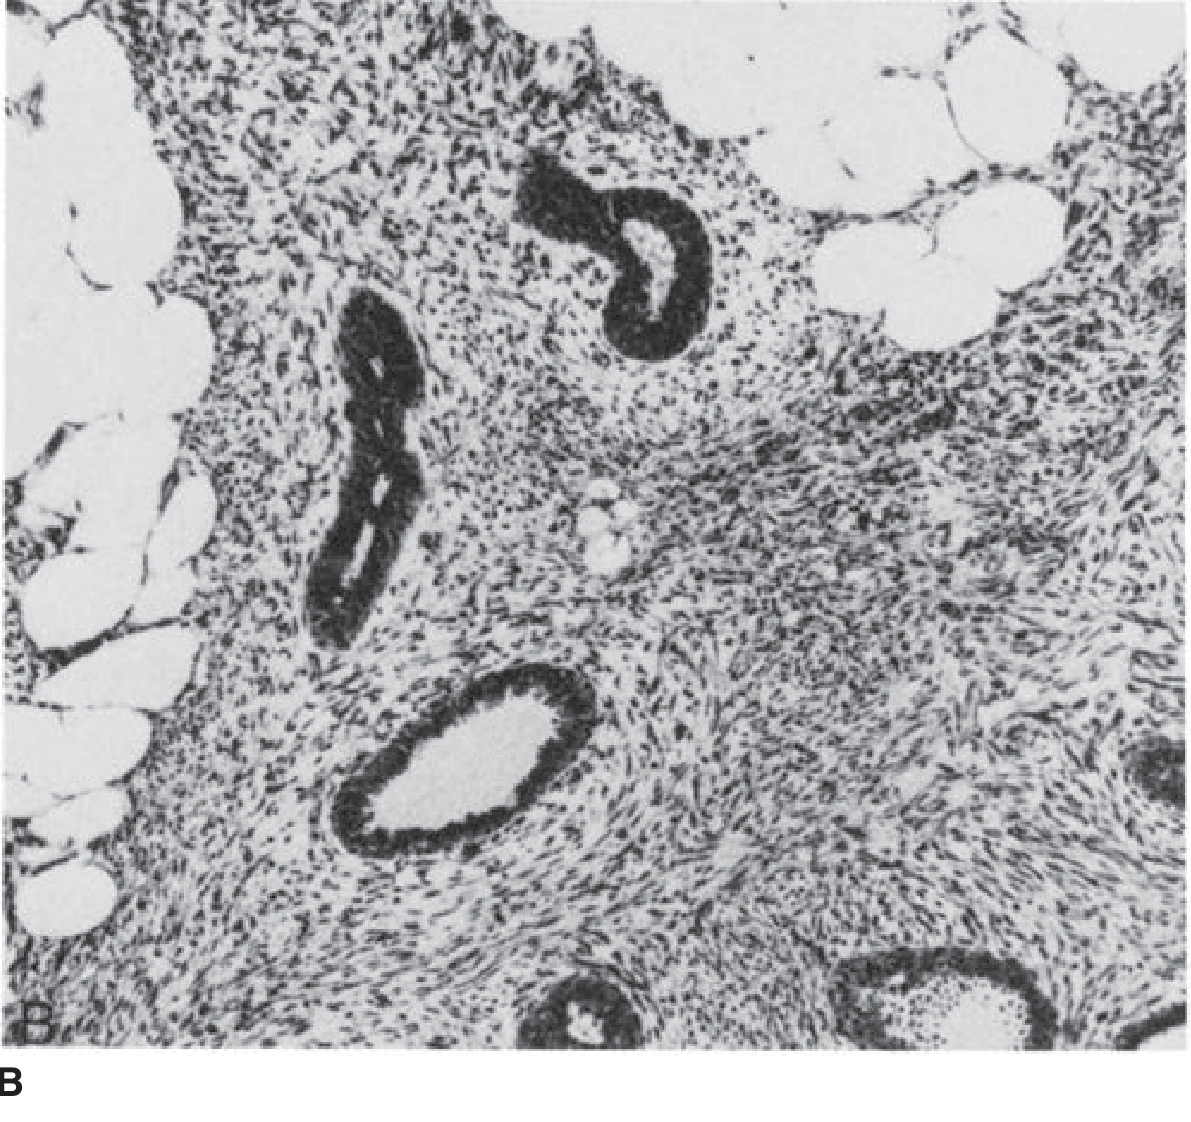

The defining histologic feature is a biphasic proliferation of stroma and mammary epithelium, with elongated epithelium-lined clefts creating the leaf-like architecture.

Malignant phyllodes tumors often contain liposarcomatous or rhabdomyosarcomatous elements rather than fibrosarcomatous elements. The number of mitoses and presence of invasive foci at the tumor margin help identify malignancy.

Histology — Malignant phyllodes tumor (H&E ×100):

Histologic features of malignant phyllodes tumor showing leaf-like epithelial-lined clefts within hypercellular stroma (H&E ×100)

— Schwartz's Principles of Surgery, 11th Ed.